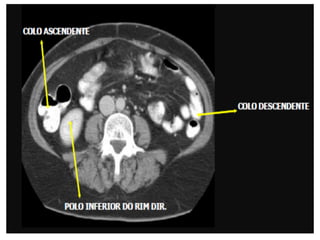

Tomografia do Abdome